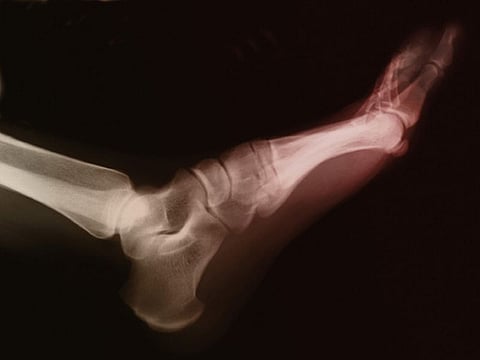

La gota es una enfermedad articular que causa dolor extremo e hinchazón y que está provocada por un exceso de ácido úrico en la sangre. Es la forma más común de artritis inflamatoria, y su incidencia ha aumentado entre los estadounidenses a lo largo de las últimas décadas, indicaron los investigadores de la Universidad de Harvard.